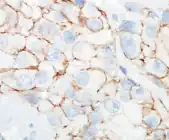

Micrographs showing each score:[46]

0

0 -

1+

1+ -

2+

2+ -

3+

3+